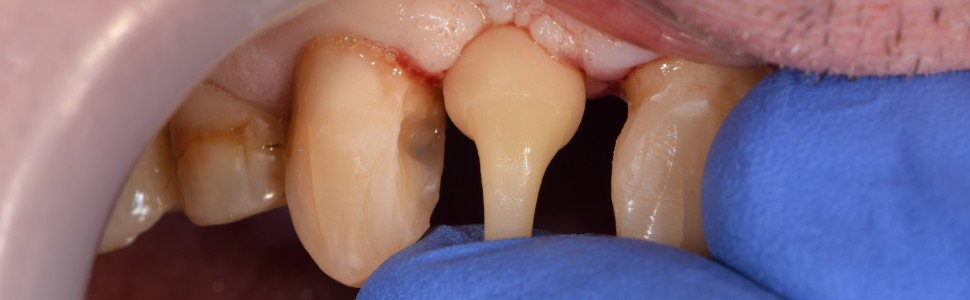

Do mojej praktyki zgłosił się 50-letni pacjent w celu ustalenia postępowania w związku z utratą 3 tygodnie wcześniej zęba 12. Przyczyną usunięcia były zapalne zmiany okołowierzchołkowe i ogólne złe rokowanie zęba (brak obręczy protetycznej). Decyzją lekarza prowadzącego wykonano ekstrakcję zęba 12, a brak korony klinicznej zęba na czas gojenia tkanek został uzupełniony nieinwazyjnym prowizorium kompozytowym, jedną porcją z materiału Gradia A3,5.